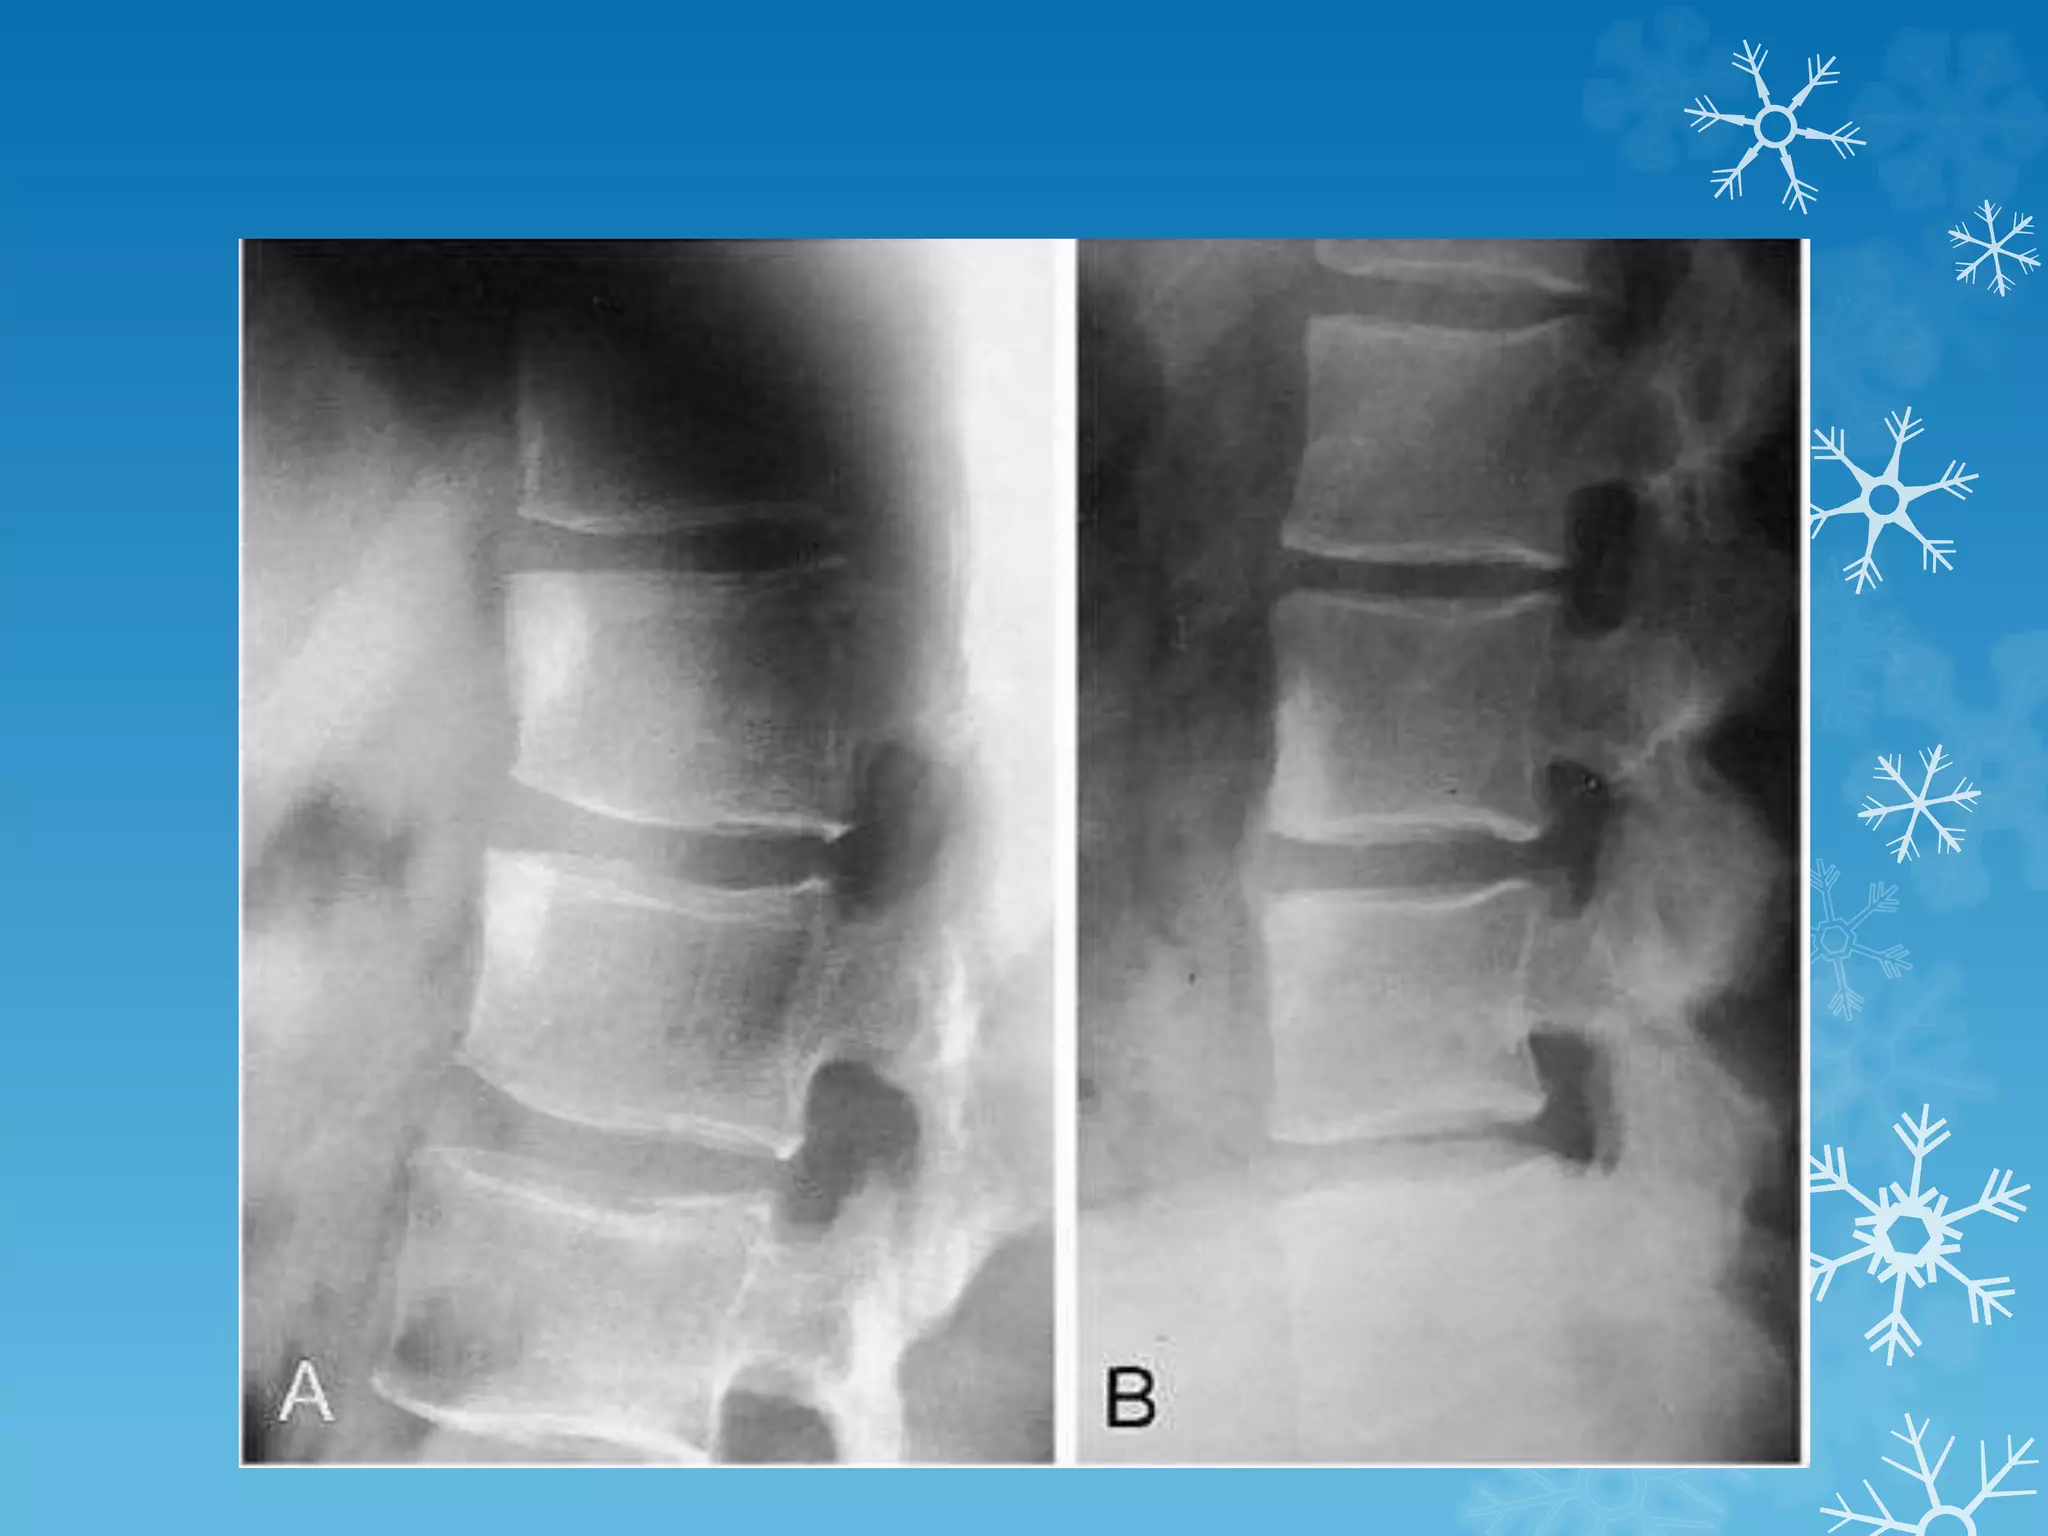

Shiny corner sign

The shiny corner sign, also known as a

Romanus lesion, is an early spinal finding in

ankylosing spondylitis.

These represent small erosions at the

superior and inferior endplates (corners on

lateral radiograph) of the vertebral bodies,

with surrounding reactive sclerosis.

Eventually the vertebral bodies become

squared